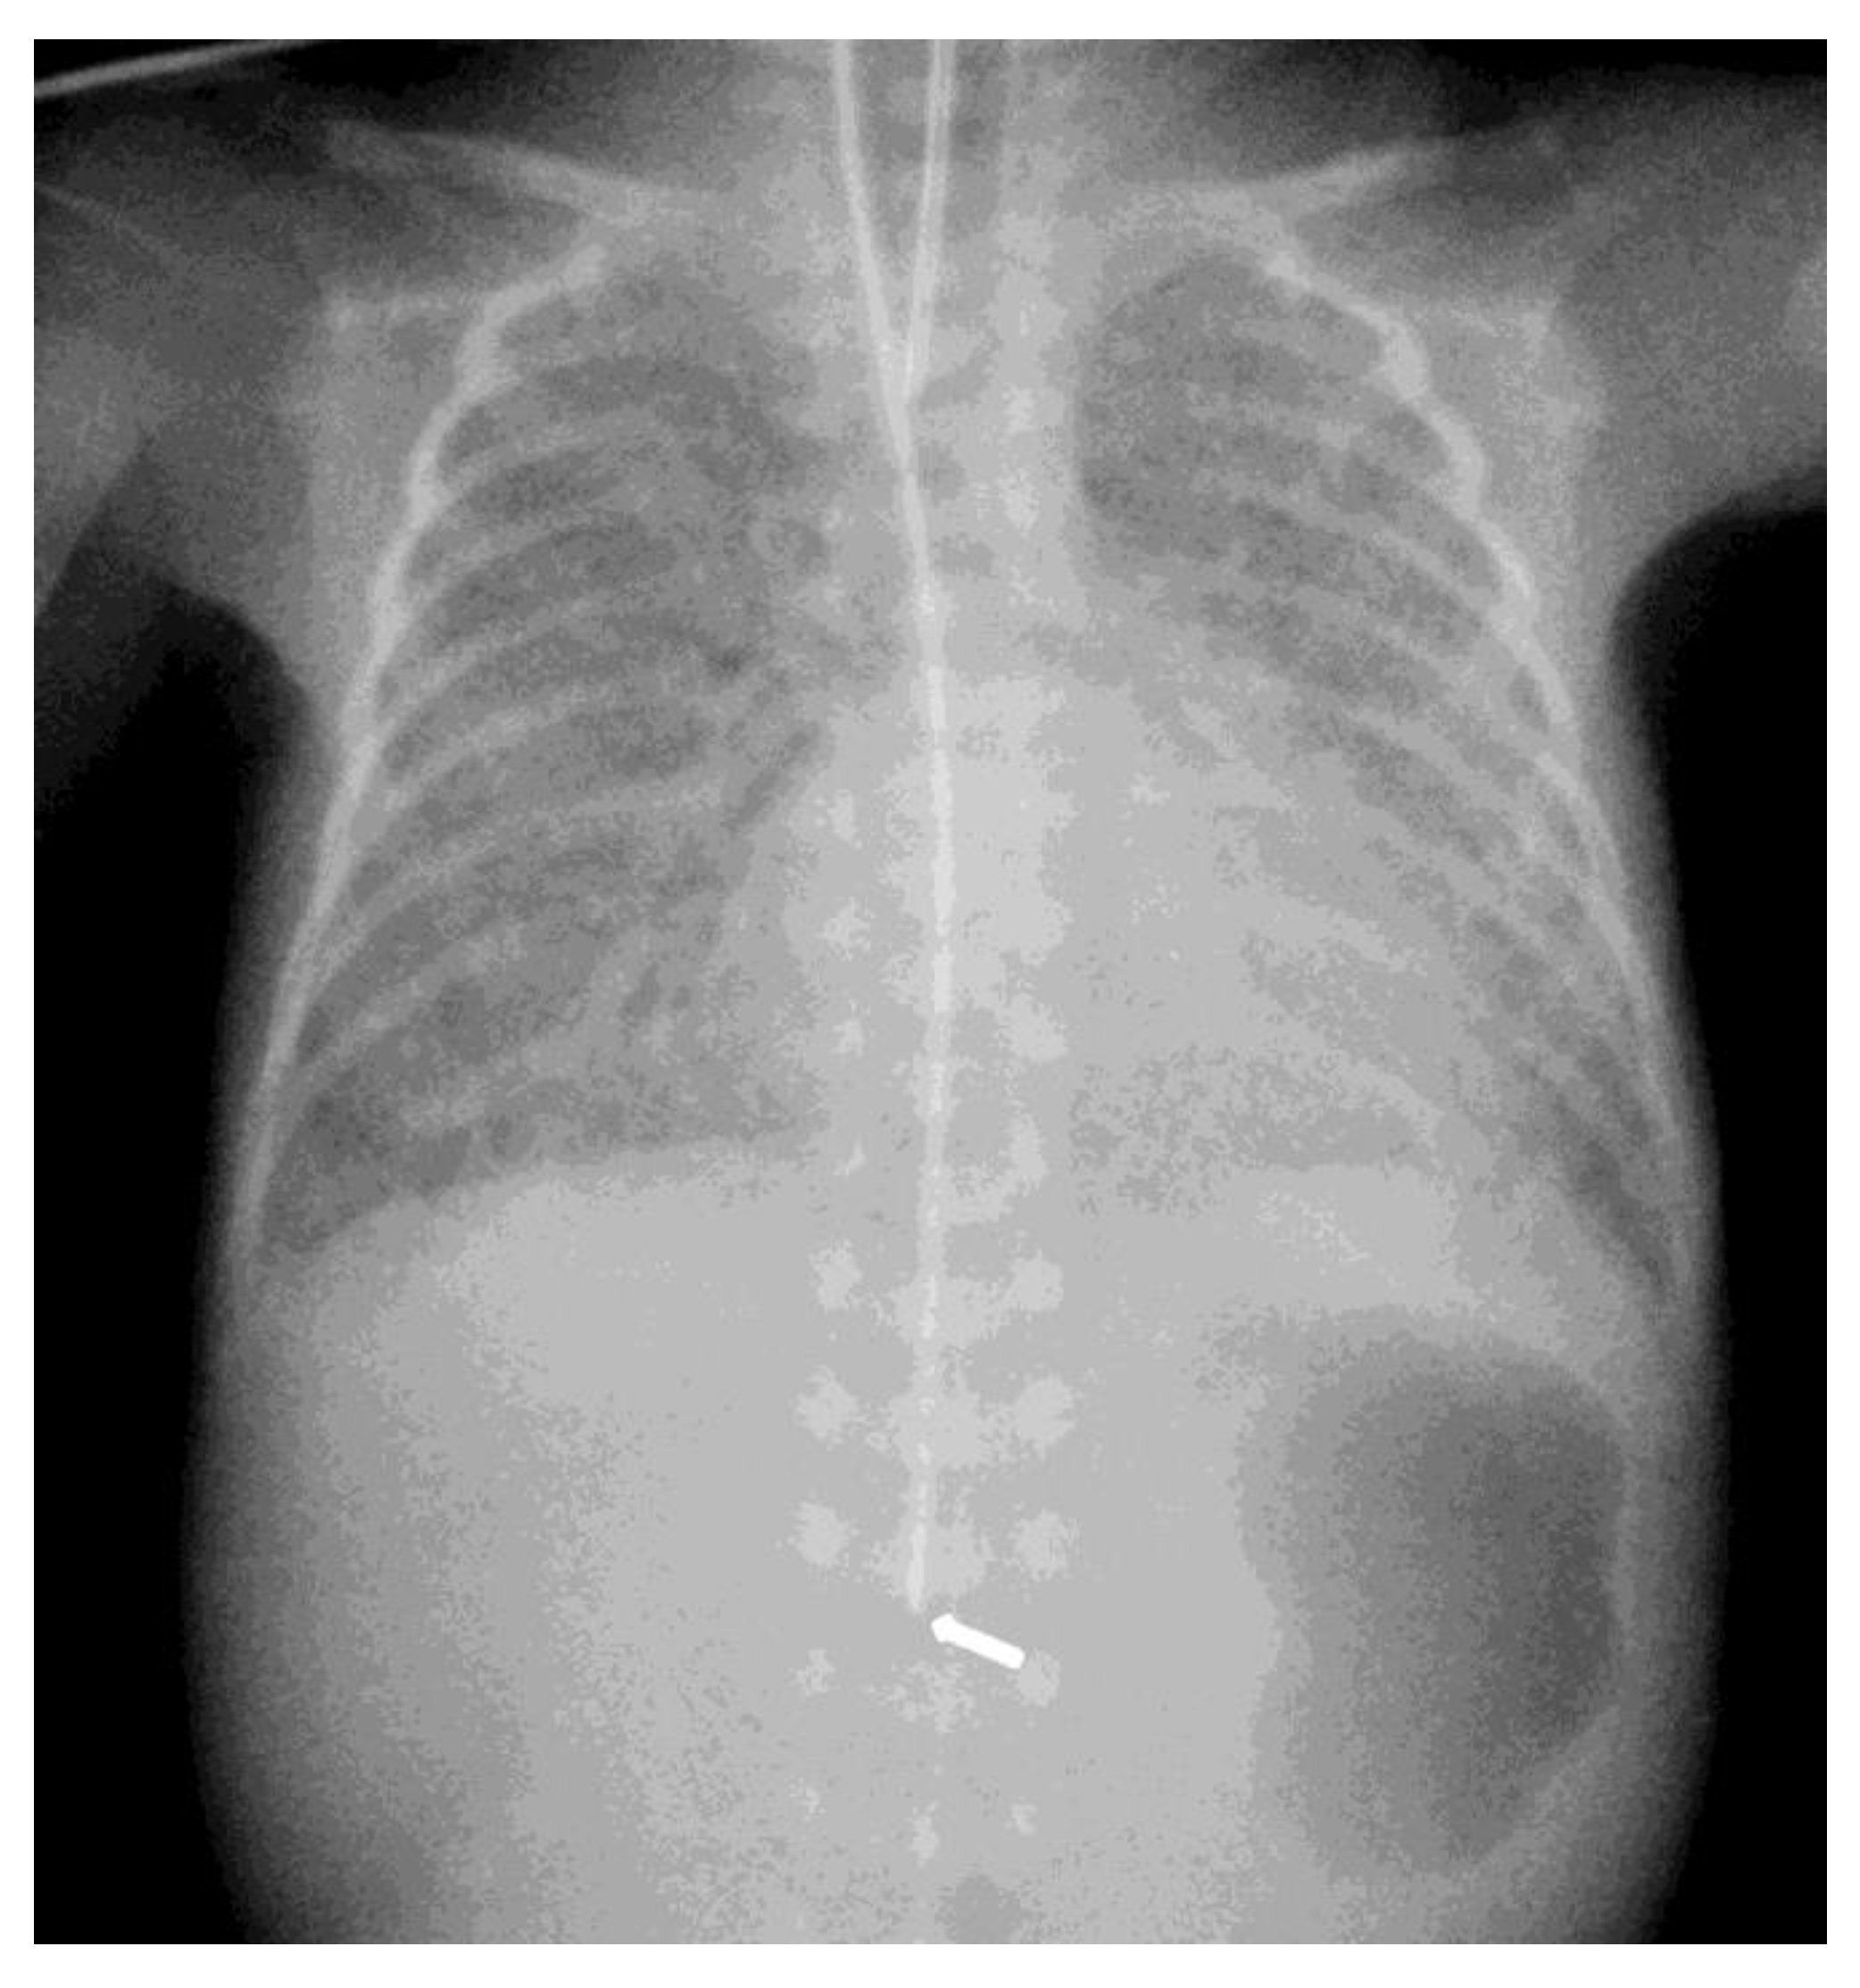

The diagnosis of EP was confirmed via the malposition of the og/ng tube in plain chest X-rays radiographic images. In infants with EP, the chest radiographic image revealed three different malpositions of the og/ng tube. In five infants, the og/ng tube was located in the right pleural cavity (pleural position) (Figure 1), which is usually connected with the pneumothorax or the pneumothorax with pleural effusion, and a radiogram of another two patients indicated mimic esophageal atresia (high position) (Figure 2). In the last three infants, the og/ng tube was located in the abdomen (low position) (Figure 3).

Radiographs of the chest are useful in demonstrating the presence of the og/ng tube in situ and might reveal three different malpositions of the nasogastric tubes, typically in the right pleural cavity associated with right-sided pneumothorax or pneumomediastinum and sometimes pleural effusion. Common symptoms in this situation are connected with the deterioration of the respiratory status. A chest radiographic image may reveal excessive amounts of air in the mediastinum. The high position of the og/ng tube mimicking an esophageal atresia effect may be due to the presence of a mass created by a false passage of air or milk in the mediastinum [9,14]. The position of the top of the og/ng tube may be helpful in differential exclusion. In true esophageal atresia, it is usually above the bifurcation of the tracheae, while in the mimic esophageal atresia, it is located below the bifurcation. In doubtful cases, esophagoscopy can be conclusive [15]. The presence of gas along the og/ng tube may also be helpful in diagnosing EP. The third possible malposition of the og/ng tube involves the intra-abdominal location, which might be associated with the absence of gas in the intestines. It must be noted that a radiographic image cross-table lateral might, in this case, indicate where the tip of the og/ng tube would appear in the posterior/retroperitoneal space. This would be advisable for a more precise diagnosis. Another complication described by Sorens was mediastinal abscess requiring chest drain insertion [16]. Occasionally, patients with intra-abdominal EP might present symptoms of peritonitis or dysphagia and drooling [1]. In our study, like Elgendys’ study, pneumothorax and septicemia were frequent complications of esophageal perforation [17]. We diagnosed peritonitis in one patient and necrotizing enterocolitis in one patient. In one patient, cardiorespiratory decompression was connected to pleural milky effusion. Chylothorax should be considered and excluded upon differential diagnosis when milk is present in the pleural cavity and milky fluid can be aspirated from the right pleural cavity. Kairamkonda linked chylothorax with esophageal perforation, which may follow when the value of the laboratory fluid analyzed shows a triglyceride level of >1.1 mmol/l with absolute cell count > 1000 cells/mcl and lymphocyte fraction > 80% [18,19,20].

Figure 2. Supine AP view of the chest and upper abdomen. The nasogastric tube tip is in a high position below the carina (arrowhead) and can mimic esophageal atresia. Gas outside the esophagus resulted from its rupture (arrow). The umbilical line is present.